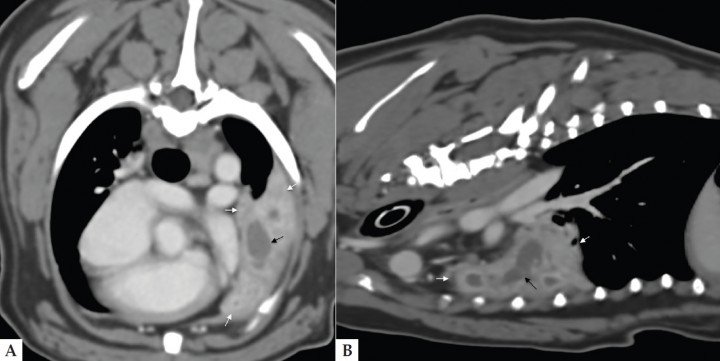

Como prueba definitiva de diagnóstico se recurrió a la tomografía computarizada (TC), en la que se observó una terminación abrupta del bronquio principal de la porción craneal del lóbulo pulmonar craneal izquierdo, confirmando así la sospecha de torsión (Fig. 4). El lóbulo afectado presentaba atelectasia severa y un árbol bronquial dilatado y relleno de líquido (Fig. 5). Tras la administración de contraste intravenoso no se observaron venas y arterias pulmonares normales porque, al igual que el bronquio, terminaban abruptamente a nivel del hilio. Asimismo, la distribución periférica de contraste y el realce pleural sugerían la presencia de pleuritis, adherencias y necrosis pulmonar, indicando que los cambios eran muy crónicos, lo que podría complicar la cirugía.

<p>Imágenes de TC de tórax en los planos axial (A) y sagital (B) y ventana de tejido blando. El lóbulo pulmonar craneal izquierdo está completamente consolidado (flechas blancas), excepto por una pequeña zona en la parte caudal que permanece aireada. Distal a la terminación abrupta del bronquio principal izquierdo se observa una estructura tubular rellena de líquido dentro del pulmón consolidado (flecha negra). Esto es compatible con el árbol bronquial dilatado y relleno de líquido.</p>

Imágenes de TC de tórax en los planos axial (A) y sagital (B) y ventana de tejido blando. El lóbulo pulmonar craneal izquierdo está completamente consolidado (flechas blancas), excepto por una pequeña zona en la parte caudal que permanece aireada. Distal a la terminación abrupta del bronquio principal izquierdo se observa una estructura tubular rellena de líquido dentro del pulmón consolidado (flecha negra). Esto es compatible con el árbol bronquial dilatado y relleno de líquido.